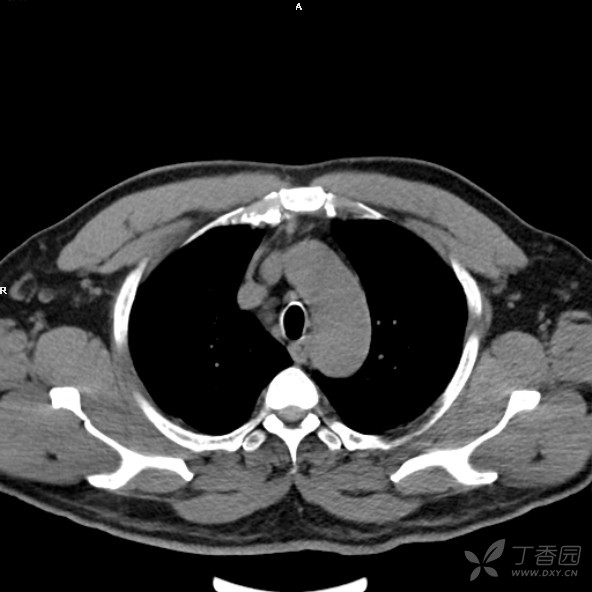

ct:前上纵隔内见-结节状不均匀的软组织密度影,大小约:15.3mm x 23.

图片尺寸1280x1090